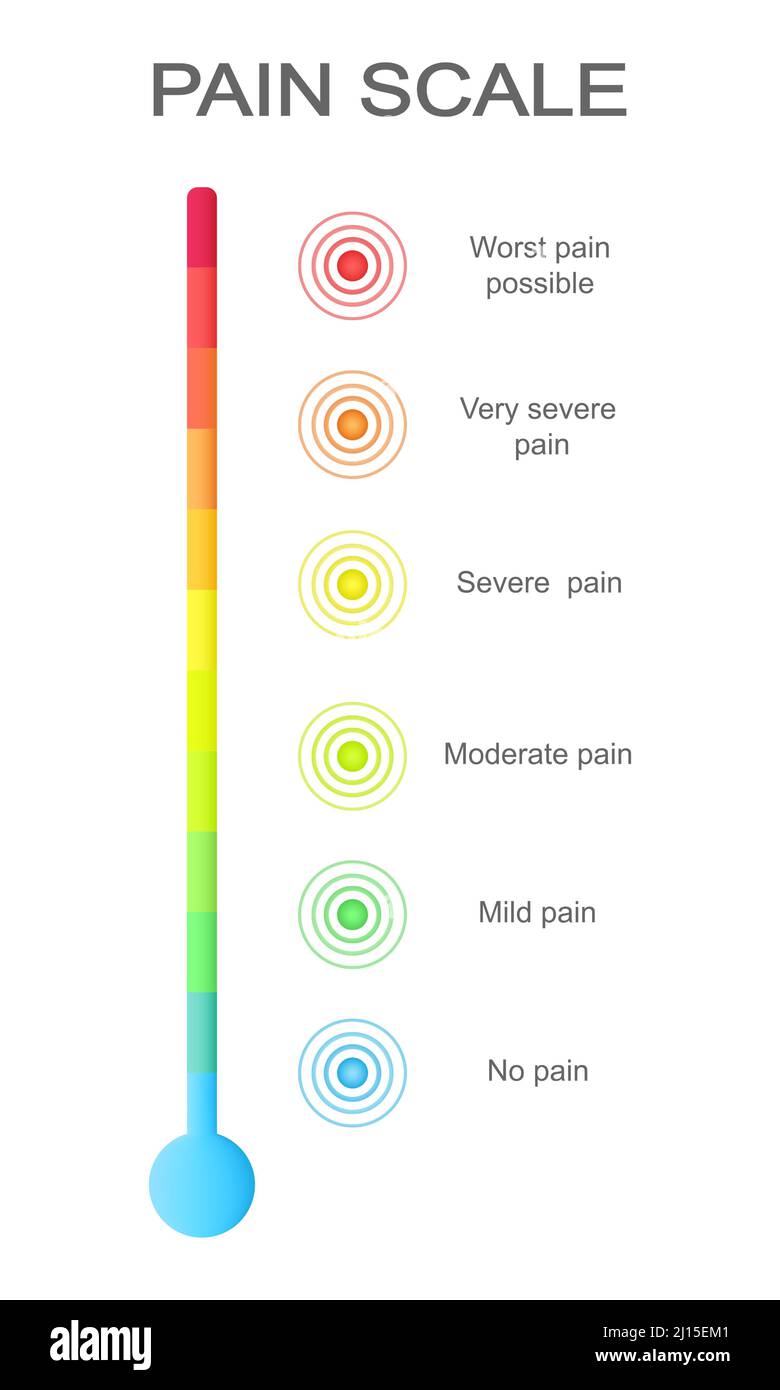

Schmerzmessskala mit mehrfarbigen Schmerzpunkten. Verletzte Messwertstände mit konzentrischen Anzeichen für die Lokalisierung von Schmerzen. Medizinisches Kommunikationstool für das Screening von Patientenerkrankungen. Vektorgrafik Stock Vektorhttps://www.alamy.de/image-license-details/?v=1https://www.alamy.de/schmerzmessskala-mit-mehrfarbigen-schmerzpunkten-verletzte-messwertstande-mit-konzentrischen-anzeichen-fur-die-lokalisierung-von-schmerzen-medizinisches-kommunikationstool-fur-das-screening-von-patientenerkrankungen-vektorgrafik-image464195801.html

Schmerzmessskala mit mehrfarbigen Schmerzpunkten. Verletzte Messwertstände mit konzentrischen Anzeichen für die Lokalisierung von Schmerzen. Medizinisches Kommunikationstool für das Screening von Patientenerkrankungen. Vektorgrafik Stock Vektorhttps://www.alamy.de/image-license-details/?v=1https://www.alamy.de/schmerzmessskala-mit-mehrfarbigen-schmerzpunkten-verletzte-messwertstande-mit-konzentrischen-anzeichen-fur-die-lokalisierung-von-schmerzen-medizinisches-kommunikationstool-fur-das-screening-von-patientenerkrankungen-vektorgrafik-image464195801.htmlRF2HY5XDD–Schmerzmessskala mit mehrfarbigen Schmerzpunkten. Verletzte Messwertstände mit konzentrischen Anzeichen für die Lokalisierung von Schmerzen. Medizinisches Kommunikationstool für das Screening von Patientenerkrankungen. Vektorgrafik

Schmerzskala mit konzentrischen Schmerzpunkten von blau bis rot. Verletzte Meterwerte mit mehrfarbigen Lokalisierungszeichen der Schmerzen. Medizinisches Tool für das Screening von Patientenerkrankungen. Vektorgrafik Cartoon-Illustration Stock Vektorhttps://www.alamy.de/image-license-details/?v=1https://www.alamy.de/schmerzskala-mit-konzentrischen-schmerzpunkten-von-blau-bis-rot-verletzte-meterwerte-mit-mehrfarbigen-lokalisierungszeichen-der-schmerzen-medizinisches-tool-fur-das-screening-von-patientenerkrankungen-vektorgrafik-cartoon-illustration-image467129079.html

Schmerzskala mit konzentrischen Schmerzpunkten von blau bis rot. Verletzte Meterwerte mit mehrfarbigen Lokalisierungszeichen der Schmerzen. Medizinisches Tool für das Screening von Patientenerkrankungen. Vektorgrafik Cartoon-Illustration Stock Vektorhttps://www.alamy.de/image-license-details/?v=1https://www.alamy.de/schmerzskala-mit-konzentrischen-schmerzpunkten-von-blau-bis-rot-verletzte-meterwerte-mit-mehrfarbigen-lokalisierungszeichen-der-schmerzen-medizinisches-tool-fur-das-screening-von-patientenerkrankungen-vektorgrafik-cartoon-illustration-image467129079.htmlRF2J3YFWB–Schmerzskala mit konzentrischen Schmerzpunkten von blau bis rot. Verletzte Meterwerte mit mehrfarbigen Lokalisierungszeichen der Schmerzen. Medizinisches Tool für das Screening von Patientenerkrankungen. Vektorgrafik Cartoon-Illustration

Vertikale Schmerzmessskala mit mehrfarbigen konzentrischen Kreisen. Verletzungen von Messwerten mit Schmerzen Lokalisierungspunkte Zeichen. Medizinisches Tool für das Screening von Patientenerkrankungen. Vektorgrafik Cartoon-Illustration Stock Vektorhttps://www.alamy.de/image-license-details/?v=1https://www.alamy.de/vertikale-schmerzmessskala-mit-mehrfarbigen-konzentrischen-kreisen-verletzungen-von-messwerten-mit-schmerzen-lokalisierungspunkte-zeichen-medizinisches-tool-fur-das-screening-von-patientenerkrankungen-vektorgrafik-cartoon-illustration-image465415889.html

Vertikale Schmerzmessskala mit mehrfarbigen konzentrischen Kreisen. Verletzungen von Messwerten mit Schmerzen Lokalisierungspunkte Zeichen. Medizinisches Tool für das Screening von Patientenerkrankungen. Vektorgrafik Cartoon-Illustration Stock Vektorhttps://www.alamy.de/image-license-details/?v=1https://www.alamy.de/vertikale-schmerzmessskala-mit-mehrfarbigen-konzentrischen-kreisen-verletzungen-von-messwerten-mit-schmerzen-lokalisierungspunkte-zeichen-medizinisches-tool-fur-das-screening-von-patientenerkrankungen-vektorgrafik-cartoon-illustration-image465415889.htmlRF2J15EM1–Vertikale Schmerzmessskala mit mehrfarbigen konzentrischen Kreisen. Verletzungen von Messwerten mit Schmerzen Lokalisierungspunkte Zeichen. Medizinisches Tool für das Screening von Patientenerkrankungen. Vektorgrafik Cartoon-Illustration